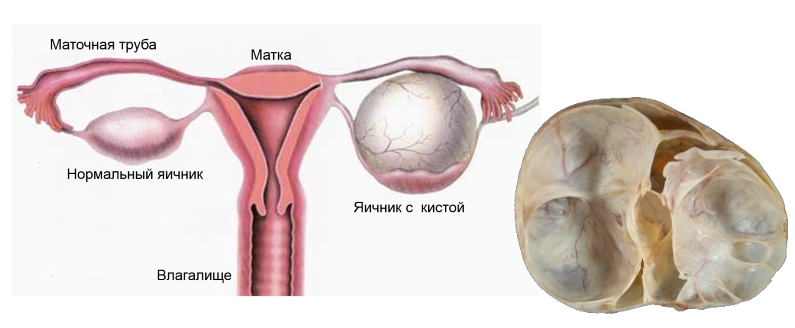

Гистологические изображения фолликулярной кисты яичника